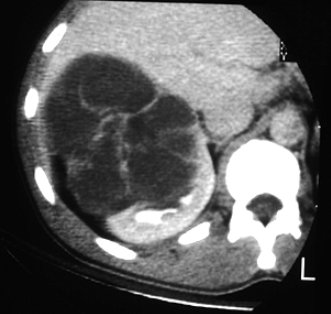

Category IV

Single axial contrast-enhanced CT scan through the right kidney demonstrates a large, multiloculated cystic mass containing irregular septations.